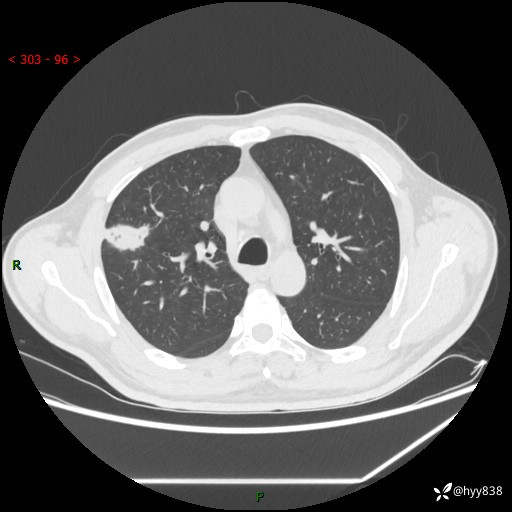

现病史:患者2天前体检完善胸部CT提示:右上肺团块影,炎症可能,肿瘤性病变不除外,冠状动脉钙化,无咳嗽、咳痰,无寒战发热,无恶心、呕吐等其他特殊不适,未予以特殊治疗,现为明确病变性质来我院就诊,门诊以“肺肿物性质待查”收入我科。 起病以来,患者精神、饮食、睡眠可,大小便正常,体力体重较前无明显变化。

胸部CT平扫+增强